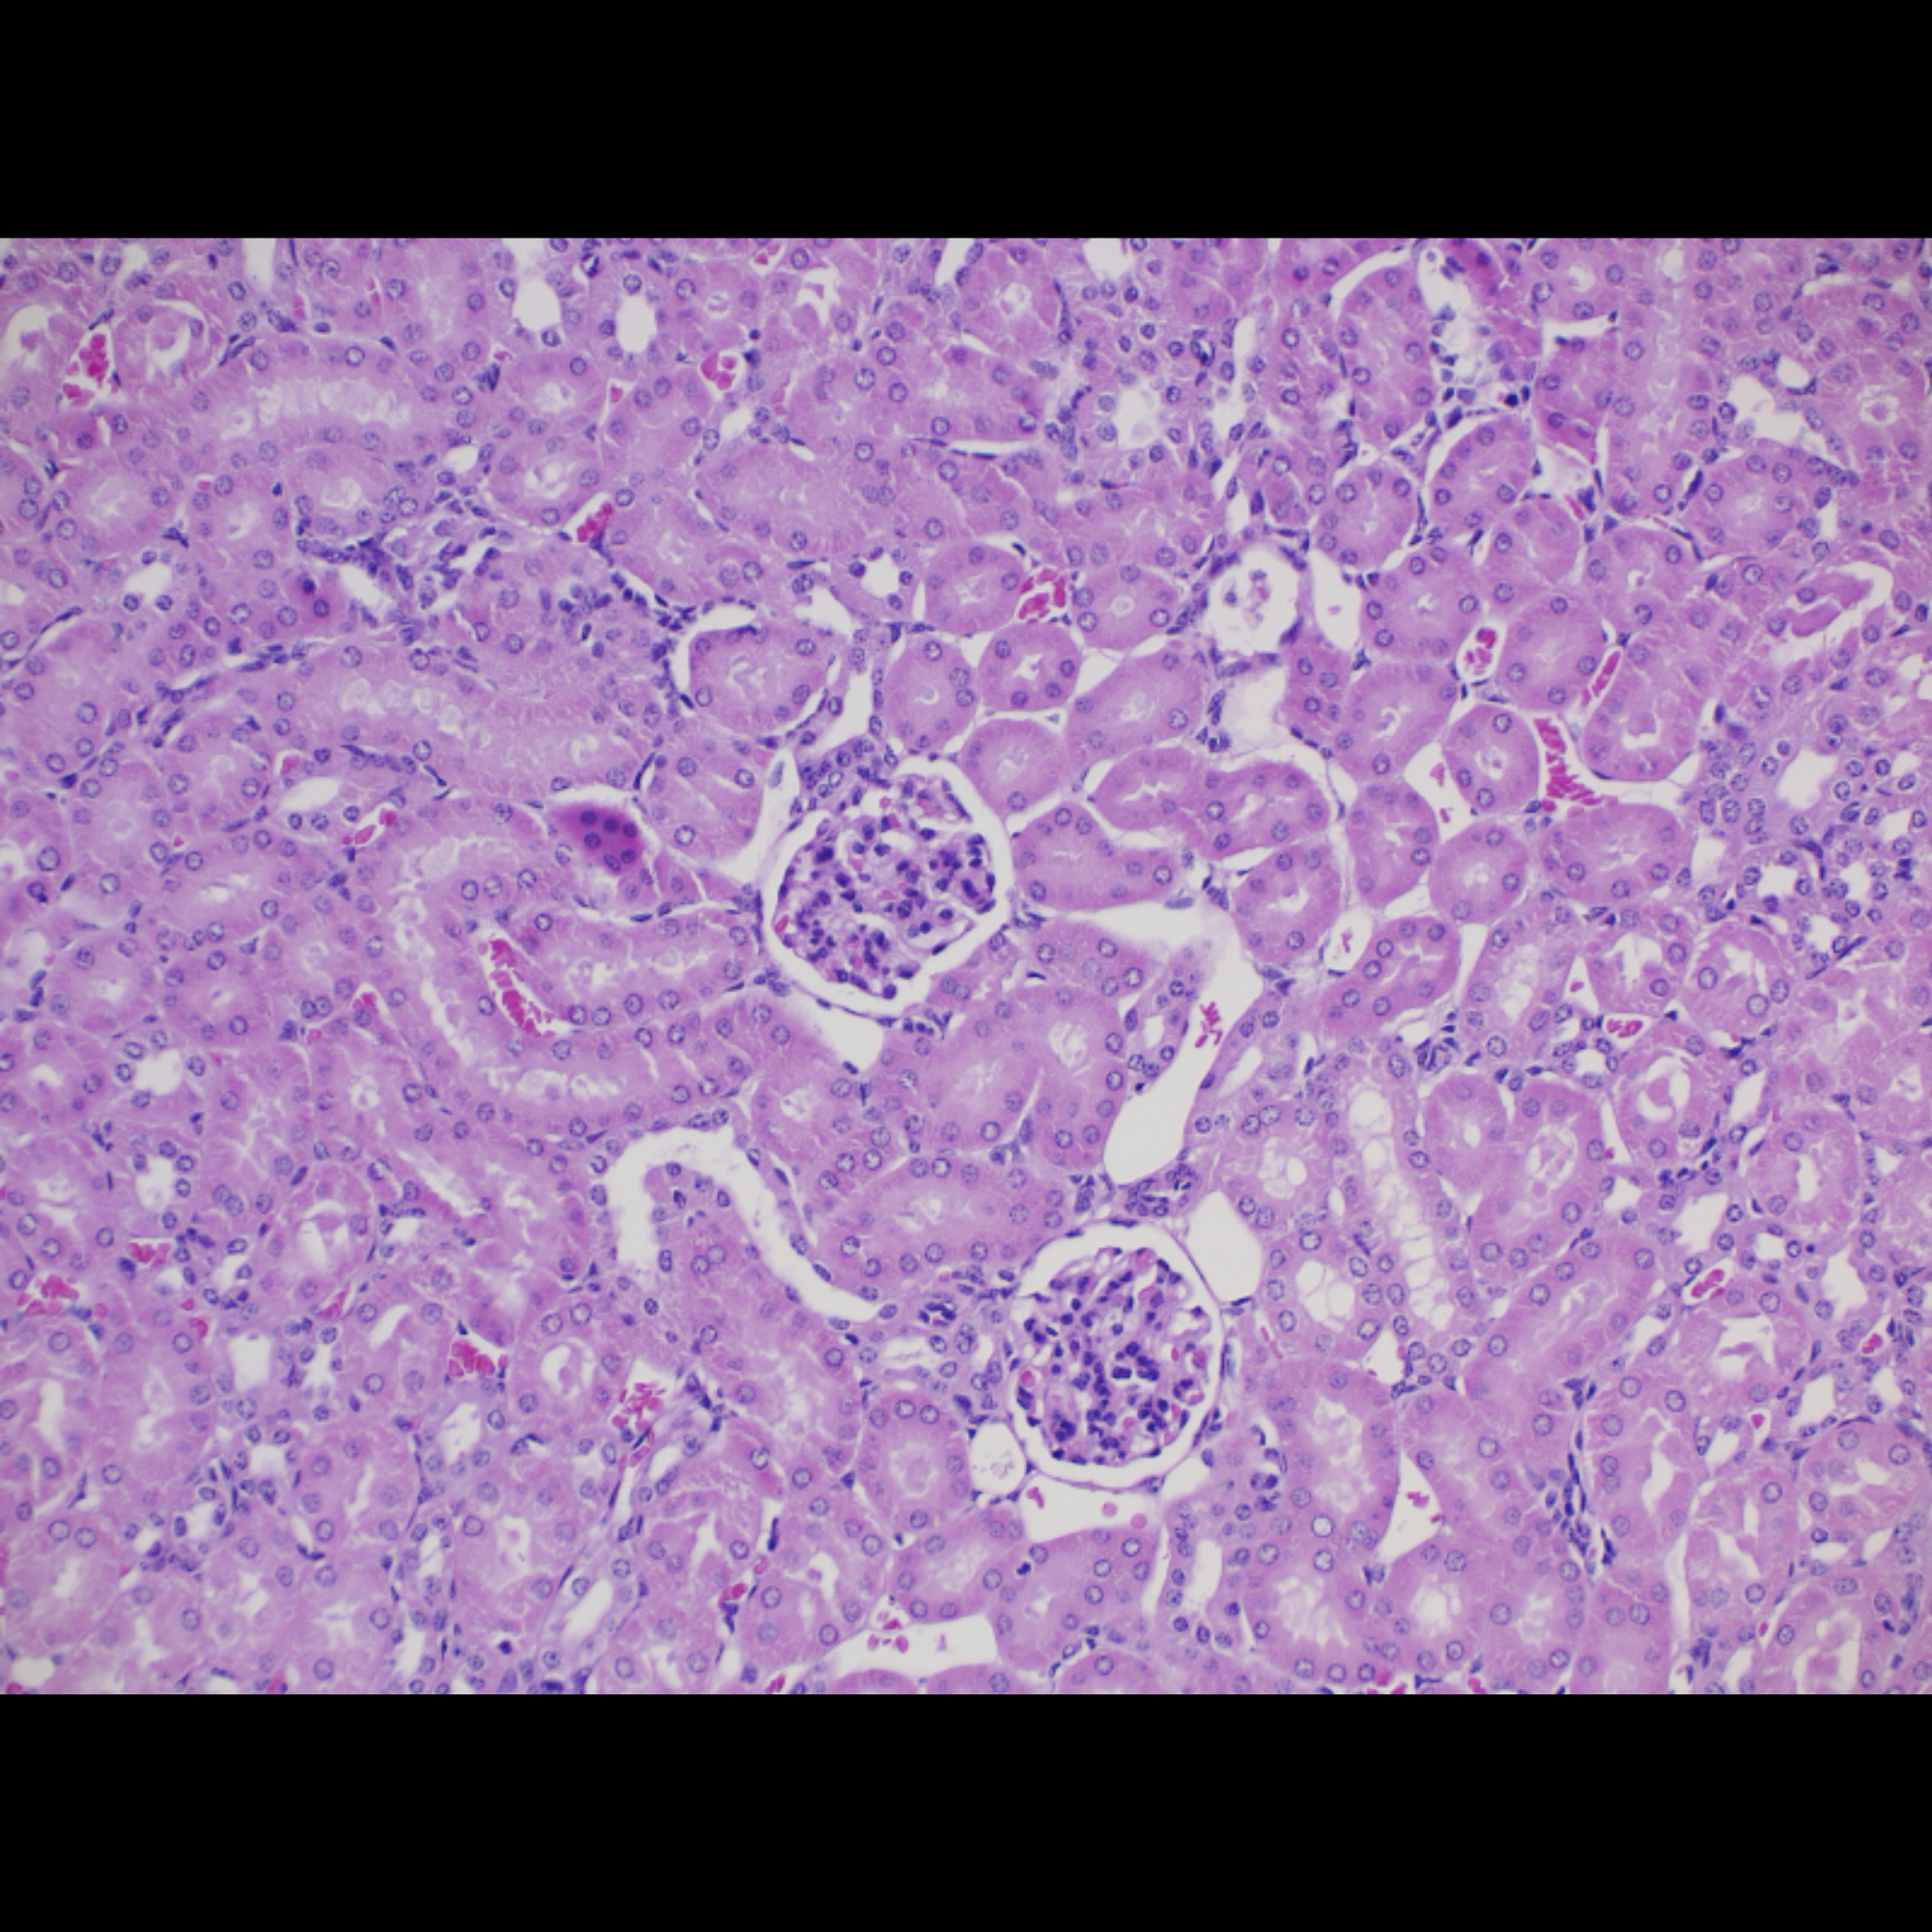

教授细胞语言

凭借直观的操作和出色的图像质量,Axioscope 5可帮助学生解读复杂的组织特征,并从第一天起就培养诊断技能。

Axiolab 5可帮助学生为实际实验室工作做好准备,支持细胞生物学、组织染色、记录等方面的教育。

• 非常适合组织学、病理学和生物医学实验室技能教学